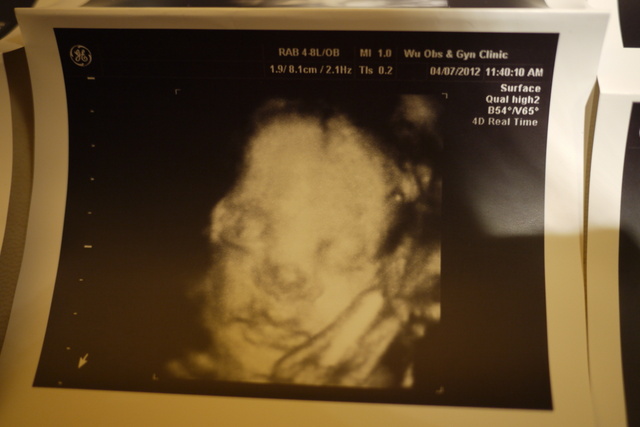

第21 ( 第六月 )

出了!!!!!!!!!!

而且鼻子和嘴唇看得很清楚!!!! ( 嘛噘嘴啦~~~爸爸!!!! )

重量大概跟大水梨差不多~~~~